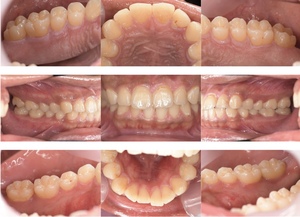

before

症例

after

歯周病検査(治療前)

歯周病検査(治療後)

レントゲン写真

基本情報

年齢・性別 32歳・男性

主訴 主訴:歯ぐきから出血する

治療部位:全顎

治療内容 「全顎」

歯周基本治療(歯周精密検査、スケーリング、OHI、SRP)

治療期間 約3ヶ月

治療費 歯周基本検査:約600円(保険診療3割負担)

スケーリング、OHI:約2,000円(保険診療3割負担)×2回

SRP、OHI:約1,500円(保険診療3割負担)×4回

歯周精密検査:約1,200円(保険診療3割負担)×2回

合計金額13,000円

(2025年2月現在)

リスク・副作用 歯石を取った後に、歯がしみることがあります。

治療方針 ①検査

レントゲン、口腔内写真を撮影して、歯や歯周組織の状態を確認します。

また、歯周病の検査で歯周ポケットの深さや出血の有無を確認します。

②スケーリング、OHI(口腔衛生指導)

スケーリングをして歯の表面の歯石を除去します。

また、正しい歯磨きの仕方や、フロスの通し方を一緒に確認します。

③歯周精密検査

前回歯石除去と歯磨き指導を行なった結果、歯ぐきの状態がどれぐらい改善したか検査します。

④SRP

歯ぐきの内側についてる歯石を除去します。

⑤歯周精密検査

SRP後、歯周病が改善されたか、検査します。

歯周ポケットが4ミリ以上の部位は、再度SRPを行います。

今回は歯周病の状態が安定したため、3ヶ月おきの定期検診で歯周病の再発や進行を防ぎます。

特記事項 歯周精密検査について:

・歯周ポケットが4ミリ以上ある場合は歯周病で、3ミリ以下は健康な歯ぐきです。

・出血の有無で炎症があるか確認します。

・磨き残しがある部分を確認して記録します。

担当者所見 初診時は、写真を見て分かるように、歯ぐきが赤く腫れていました。

また、歯周病の検査では、全体的に歯と歯の間の部分の歯周ポケットが4ミリあり、全体の約81%から出血が認められました。

出血量も多く、歯ぐきに触れた瞬間に出血しました。

レントゲンで骨のレベルがしっかりとあることが確認できました。

そのため、ご自身で正しい歯磨きを継続することで改善すると考えました。

歯周基本治療を経て、再度検査した結果、歯周ポケットはほぼ3ミリ以下に改善しました。左下7番の残存した歯周ポケットは、隣の親知らずを抜いたため経過観察します。

出血率は約4%まで改善し、出血量も点状で少なくなりました。

今後は右上2番、右下3番の歯ぐきの発赤の改善と、出血率0%を目指して、定期検診でメンテナンスしていきます。